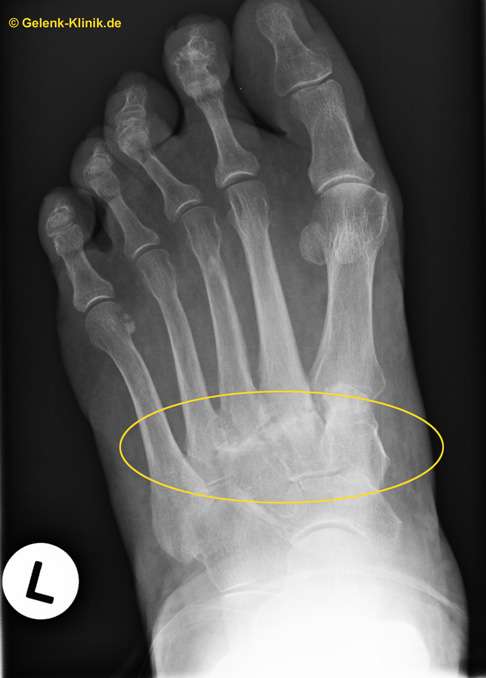

Lisfranc-Gelenk (tarsometatarsales Gelenk, gelbes Oval) einer 70-jährigen Patientin mit Arthrose im Röntgenbild. © Gelenk-Klinik

Tarsometatarsale Fraktur/Lisfranc-Fraktur im Röntgenbild: In diesem Bild sind die Fußwurzelgelenke disloziert, also nicht mehr in der normalen anatomischen Position. Das ist eine sichere Indikation zur Operation. © Case courtesy of Dr. Andrew Dixon, Radiopaedia.org

Röntgenaufnahmen der Füße in zwei Ebenen zeigen mögliche Arthrosezeichen in der Fußwurzel: Gelenkspaltverengung und Osteophyten (Knochenanbauten).